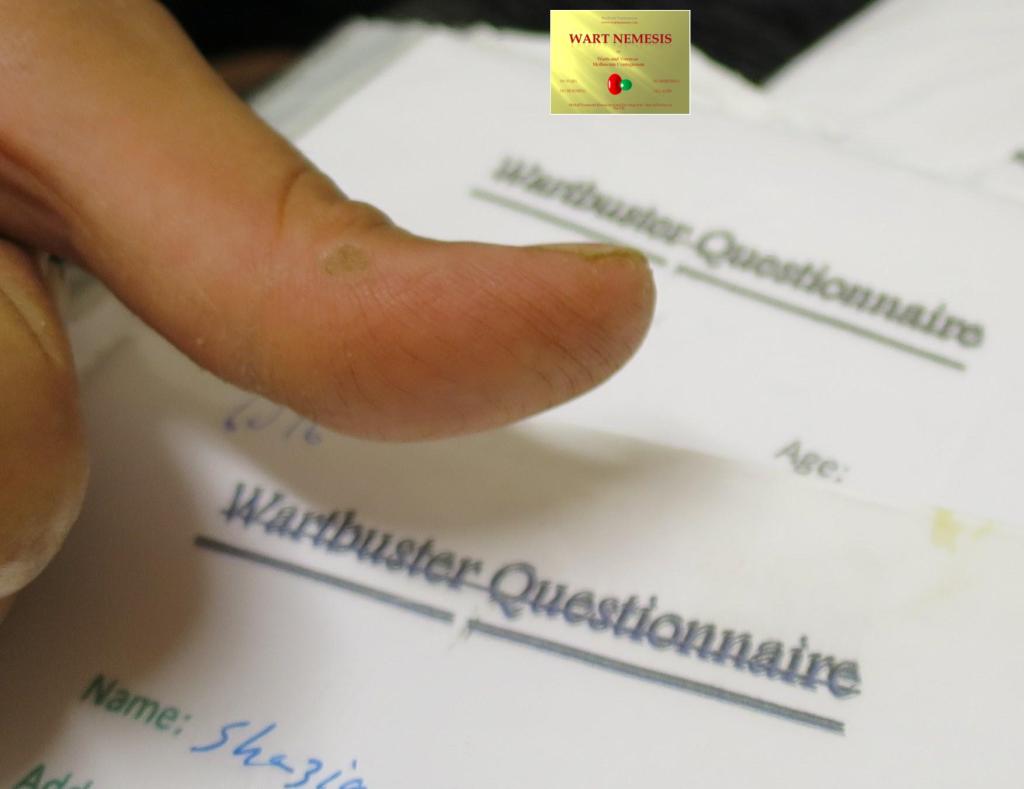

This herbal treatment is suitable for all ages and causes no skin reactions. It is for external application only and is not suitable for use around the eyes. Results are usually achieved between 1 week and 1 month after use. In the pictures below, the cream was only applied to one verrruca at the base of the left toe under a waterproof bandage. 2 weeks later the treated verruca was disappearing. 6 weeks later all the verrucae on both feet had gone. Click on the pictures to enlarge and then on the back button to return to the page.

Lesion had shrunk and vanished 4 week later

All warts from both hands cleared

Patient is now cured and immunised against Human Papilloma Virus infection preventing recurrence.